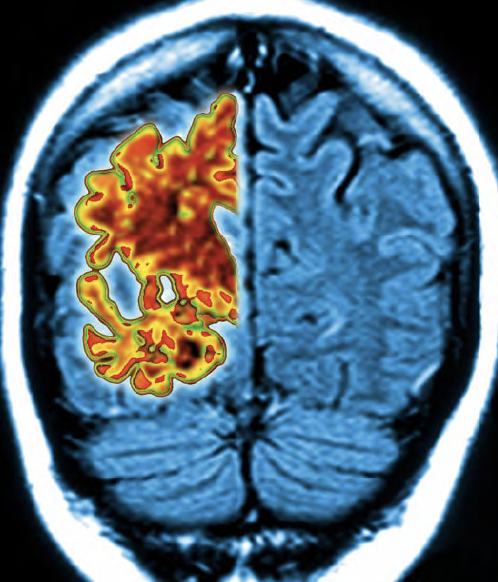

La detección de placas de ß-amiloide en el cerebro llegó a plantearse como método de cribado. Si una persona presentaba estos depósitos, que se podían visualizar mediante una tomografía por emisión de positrones (PET), cabía deducir que dentro de diez o quince años desarrollaría la enfermedad. Sin embargo, la teoría se vino abajo como un castillo de naipes.

Como explica Antonio Maldonado, jefe de Medicina Nuclear del Hospital Quirónsalud de Madrid, “se vio que había muchos pacientes que no presentaban depósitos y sí tenían alzhéimer, y a la inversa: otros presentaban placas, pero no la dolencia. Se comprobó que esos sedimentos aparecían también en boxeadores, veteranos de guerra o personas con síndrome de Down que no desarrollaron el trastorno”.

Los grandes de la industria farmacéutica, como Bayer, Novartis, Pfizer y Roche, han virado sus investigaciones en los últimos años hacia otro compuesto que también se acumula en el cerebro en forma de ovillos, la proteína tau, cuyos niveles en las neuronas se encuentran detrás de la aparición del alzhéimer. “La cantidad de placas de ß-amiloide no guardaba relación con la gravedad de la enfermedad, mientras que esta asociación sí ocurre con la proteína tau: la progresión del mal es mayor cuanta mayor es la acumulación de esta sustancia”, apunta el doctor Maldonado.

A partir de esta evidencia, la innovación farmacéutica se enfoca en desarrollar compuestos que, a través de pruebas de imagen, detecten estos sedimentos neurológicos y, a su vez, diseñar tratamientos que impidan su acumulación. Y es que el alzhéimer comienza a gestarse décadas antes de que aparezcan los primeros síntomas, de ahí la importancia de una detección precoz. En muchos hospitales, ya se emplean pruebas de imagen para descubrir los depósitos de cuerpos tau. Confirmada su presencia, se puede predecir con diez o quince años de antelación si una persona va a sufrir la enfermedad, una anticipación capital para retrasar su evolución.